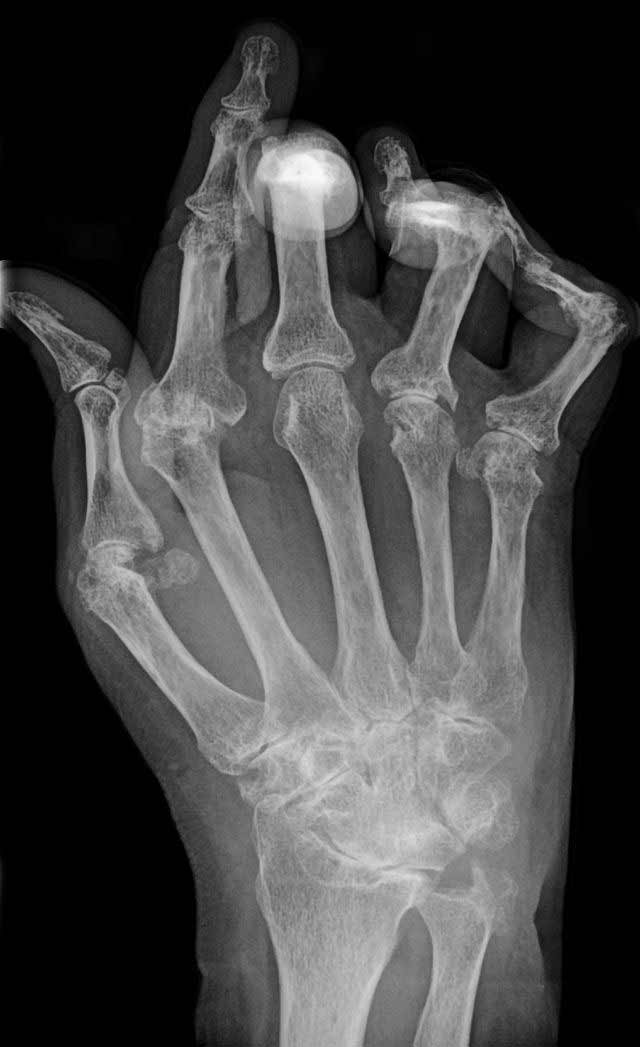

Zánětlivý proces postihuje kloubní výstelku. Dochází ke zmnožení granulační tkáně, která časem začne přerůstat na kloubní chrupavku. Chrupavku i povrch příslušného kloubu postupně ničí. Tam, kde se zánětlivý proces nepodaří včas zastavit, dochází v postižené oblasti k nepříznivým změnám, a po čase se změní nejen vzhled kloubu, ale i jeho funkce (až znehybnění kloubu).

Základním předpokladem úspěšné léčby je včasná návštěva lékaře. Revmatolog může diagnózu stanovit teprve na základě fyzikálního vyšetření, rentgenového nálezu a výsledků krevních testů.